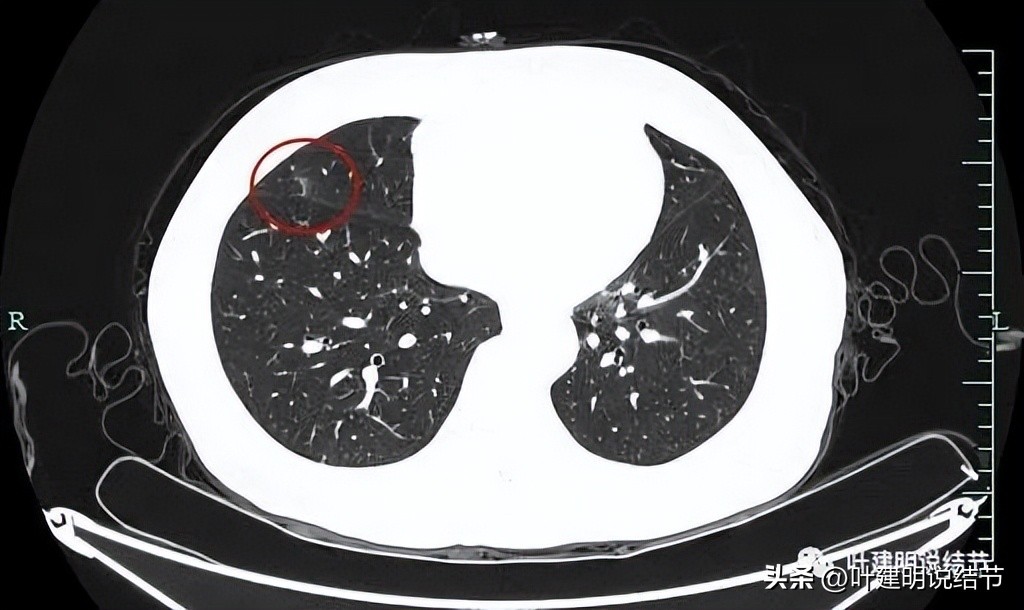

上图是右中叶的病灶,边缘偏模糊的磨玻璃影。因为最早于2018年时是报了右中叶有小结节,所以此处也要注意一下。

此灶中间有偏高密度,磨玻璃部分边缘不太清楚,显得瘤肺边界欠清。

灶内条状偏高密度可见。

叶间胸膜感觉略有点牵向病灶,但不厉害。

边缘区是磨玻璃成分,更靠胸膜处似乎还有卫星病灶。

右叶单按此次的影像来看,感觉倾向慢性炎些,毕竟收缩力弱、有卫星灶、轮廓虽清,但瘤肺边界欠清,磨玻璃部分密度较低,中间实性部分密度偏高但呈条状。